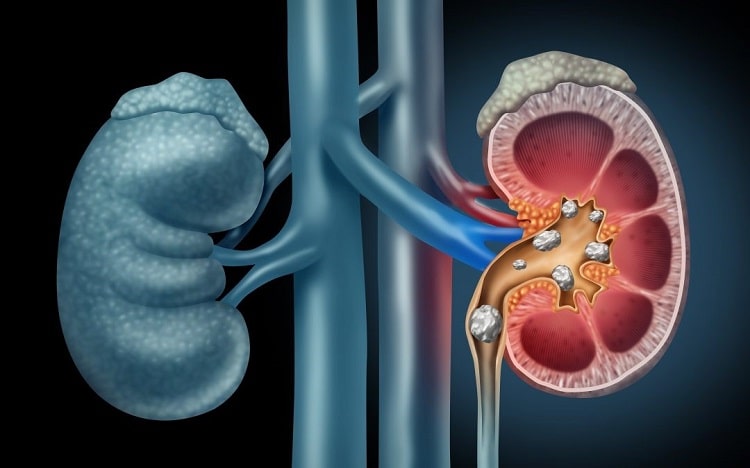

سنگ مثانه

سنگ مثانه میتواند به دلایل زیر ایجاد شود:

- در مردان، اندازه غده پروستات با پیری افزایش مییابد که میتواند فشاری بر روی مجرای ادراری اعمال کند. این فشار باعث میشود ادرار به طور کامل دفع نشود و در مثانه باقی بماند، که میتواند منجر به تشکیل سنگهای بلوری شود. این سنگها ممکن است به صورت رسوبات ادراری از بدن دفع شوند.

- عوامل مختلفی مانند التهاب در ناحیه لگن، استفاده از سوندهای ادراری، استفاده از وسایل پیشگیری از بارداری و رادیوتراپی نیز میتوانند خطر ایجاد سنگهای مثانه را افزایش دهند.

- کاهش فشار مثانه، آسیب به اعصاب مثانه، دیورتیکول مثانه و مشکلات دیگر ممکن است جریان ادرار در خانمها را مختل کنند و باقیمانده ادرار در مثانه نیز میتواند منجر به تشکیل سنگ شود که ممکن است به صورت رسوبات ادراری دفع شوند.

- در برخی موارد، سنگهای کلیه از طریق مجرای حالب به مثانه منتقل میشوند.

- سنگ کلیه